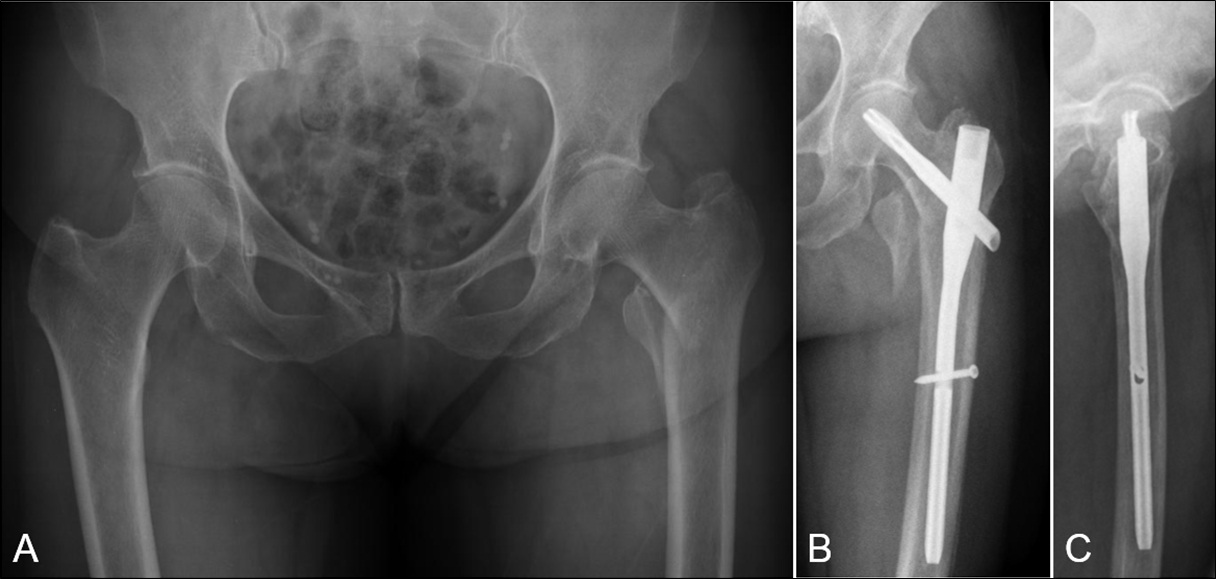

Penetración de la cortical anterolateral en fracturas de fémur proximal tratadas con clavos endomedulares cortos Reporte de dos casos. [Penetration of anterior-lateral cortex in proximal femur fractures treated with short intramedullary nails Report of two cases].

7. Ostrum RF, Levy MS. Penetration of the distal femoral anterior cortex during intramedullary nailing for subtrochanteric fractures: a report of three cases. J Orthop Trauma 2005;19:656-60.

9. Egol KA, Chang EY, Cvitkovic J, Kummer FJ, Koval KJ. Mismatch of current intramedullary nails with the anterior bow of the femur. J Orthop Trauma 2004;18:410-5.